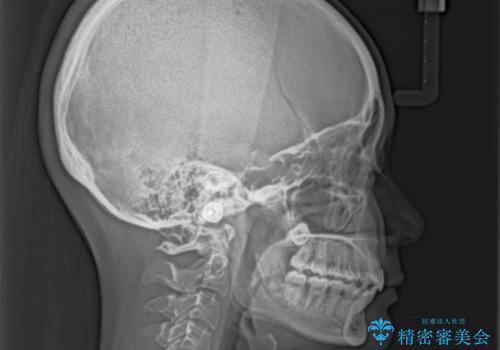

横顔は元々突出した印象ではなかったのですが、上顎前歯の角度が改善したことで、唇の閉じにくさが改善されました。